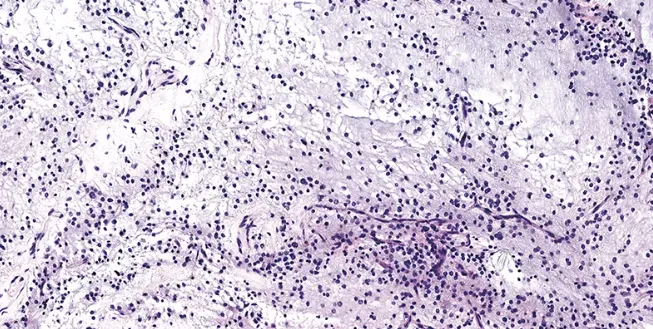

MGNT主要发生在儿童和年轻人中,临床主要表现为头痛、呕吐、癫痫发作和行为障碍。组织学上与胚胎发育不良性神经上皮肿瘤(DNT)或形成菊形团的胶质神经元肿瘤(RGNT)相似,可见黏液样基质背景中的少突胶质细胞样细胞增生,细胞核呈圆形或卵圆形、核仁小、胞质空亮或轻度嗜酸性,局部可见浮蛙样神经元。

显微镜下检查的组织学特征有哪些?

显微镜下,这种肿瘤显示低级别的少突胶质细胞样肿瘤细胞和显著的黏液样基质,有时伴有细腻的毛细血管网络和神经元样花环结构。免疫组化检测显示,GFAP、OLIG2阳性,而BRAF和FGFR1阴性。

组织学上,该肿瘤的特征是少突胶质细胞样细胞嵌入黏液样基质。其分子标志是血小板衍生生长因子受体α(platelet-derived growth factor receptor alpha,PDGFRA)突变。这类肿瘤与皮质性DNT具有不同但密切相关的DNA甲基化特征。